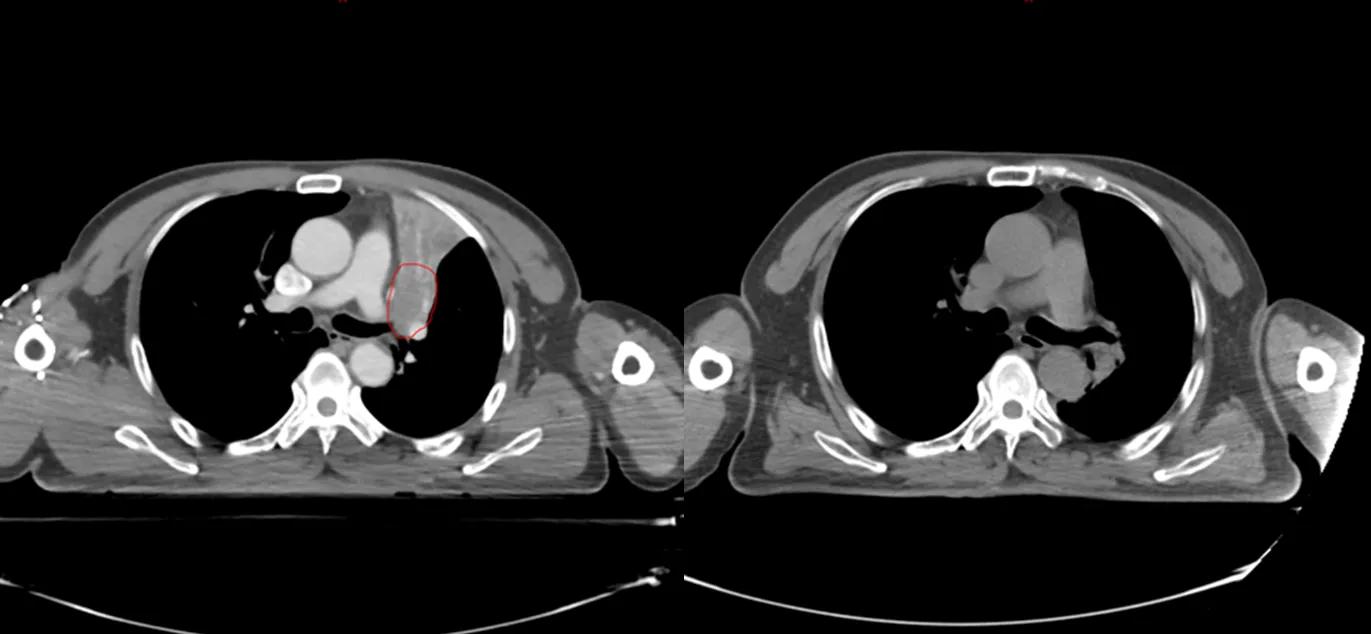

治疗前后CT对比,红色为肿瘤(左),治疗后肿瘤消失(右)

与这些名人患肺癌的同时,笔者治好了至少5位晚期肺癌病人(见下图CT片显示的肿瘤)。笔者病人有咳嗽,咯血,胸痛,胸闷,气急等症状,病人家属知道亲人是晚期肺癌,没有抱多大希望,治疗的目的只是想减轻一些症状,延长生命。经过笔者的精心治疗,2例现已活了5年多,2例已活过3年多,1例已活过2年多。治疗时年龄最大有82岁,最小年龄51岁,他们现在都生活得很好,甚至一个来自江西农村的病人一直在田地里干重体力农活。